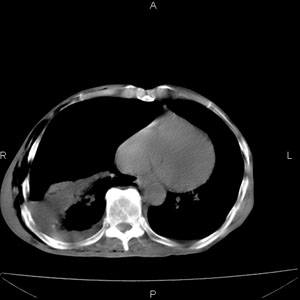

患者男,77岁,于3日前从树上摔下,头部查ct示蛛血,硬膜下出血,上腹部ct未见明显异常,右侧胸腔积液,左侧如常。肺部拍片示右侧肋骨多发骨折住院后今日来查肺部ct,我看到的是1。右侧胸腔血气胸并右肺上叶,中叶压缩性肺不张,2。右肺下叶肺挫伤并多发肋骨骨折,肌内及皮下积气3。左侧少量胸腔积液,我想请教的是3天前左侧胸腔里没有积液今天怎么出现了呢,是什么原因呢?请讨论。

回复楼主   左侧液气胸,液体来源1、肯定有血液成分,多少不一定。2、胸膜腔渗液,由于肺压缩、活动度下降,肯定胸膜吸收有问题,导致积液增多。

因为3天前病人刚摔的时候,左侧胸腔受伤不严重,故而当时没有胸腔积液,但病人受到这么大的伤害,胸膜腔内的液体动态平衡肯定会受到影响,所以过一段时间后才出现胸腔积液。